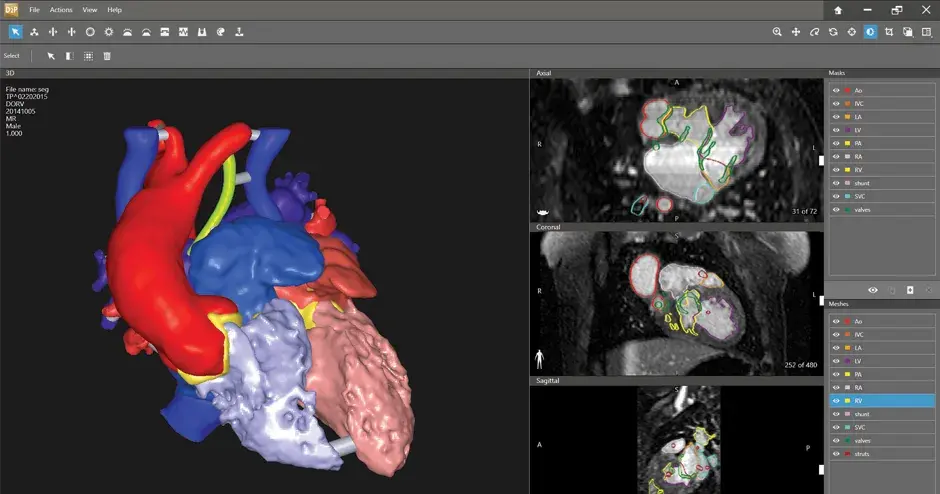

Advanced Software

DICOM에서 PRINT로

DICOM 3D 모델 소프트웨어